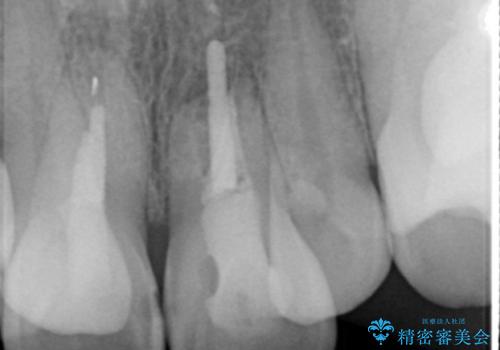

X線写真より不十分な根管治療、根尖病変、前歯の変色が認められます。

歯根の近接のみられる右上側切歯を抜去し、根管治療を伴うセラミック治療を計画します。

叢生が著しく、歯根の近接が見られる場合歯磨きができず歯石がたまりやすく骨吸収の原因となることが多いです。

このような場合矯正や転位歯の抜去が治療方法として挙げられます。